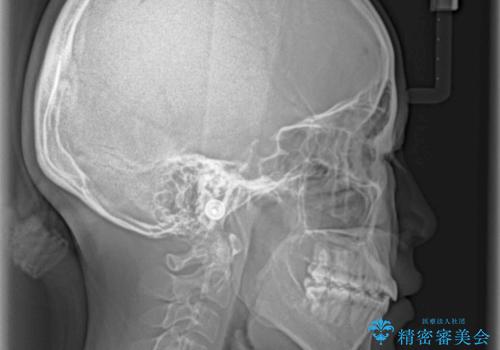

- 八重歯と上下前歯のでこぼこを気にして来院された患者様です。

上下前歯部叢生のスペース獲得のため、上下顎左右小臼歯各1歯(計4本)と全ての親知らずを抜歯して、矯正治療を行うこととしました。

上下の正中位置が大きくずれていたため、治療期間の長期化や正中が合わないまま終了することが予想されましたが、思っていた以上にスムーズに歯が移動し、満足いただける仕上がりとなりました。